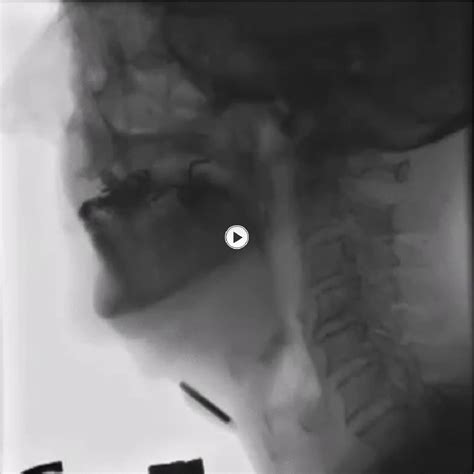

The Videofluoroscopic Swallow Study (VFSS), also known as a modified barium swallow, is a diagnostic procedure that uses fluoroscopy and a barium-based contrast material to visualize the swallowing process. This study helps identify the specific phase of swallowing that is impaired, whether it is the oral, pharyngeal, or esophageal phase.

During the study, the patient will be asked to swallow various consistencies of barium-coated food and liquids while being observed under fluoroscopy. This real-time imaging allows the healthcare team to assess the swallowing mechanism in detail.

1. The patient is positioned in front of a fluoroscopy machine, which emits X-rays to create real-time images of the swallowing process.

2. The patient is given barium-coated food and liquids of different consistencies, such as thin liquids, thick liquids, pudding, and crackers.

3. The healthcare team observes the patient’s swallowing mechanism, noting any abnormalities or difficulties.